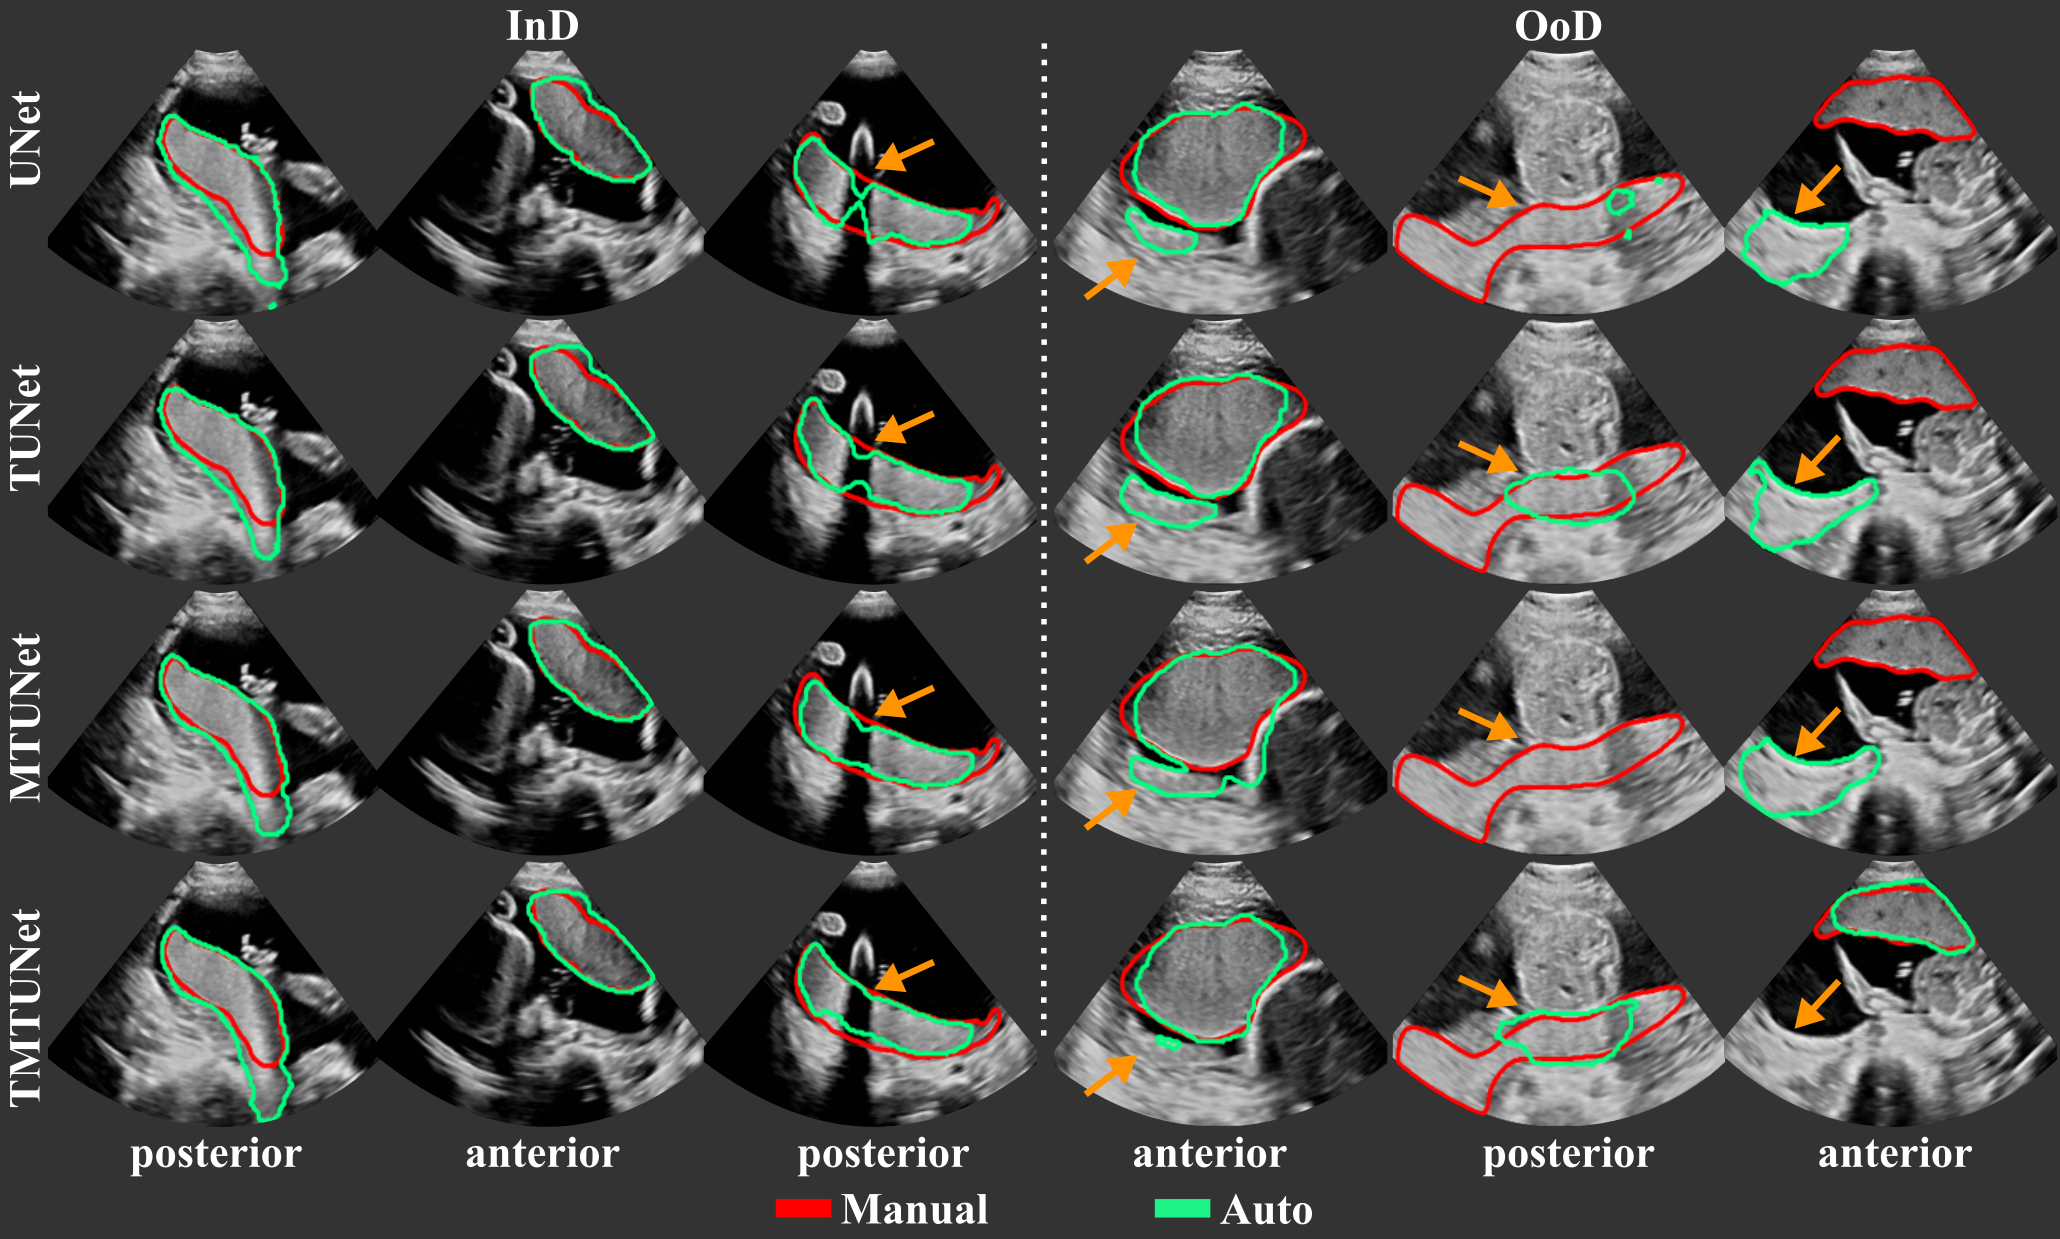

The segmentation performance of the different models measured by Dice, IoU, ASD and RHD are reported in Table 2 and representative segmentations comparing InD and OoD examples are shown in Fig. 4 with further examples in Fig. 11. Results using different training and validation sets suggest that anterior and posterior placentas represent two different distributions in the data. The baseline UNet trained on set A (only anterior) achieves a high Dice score of for the InD test set (anterior), but performs poorly on the OoD set (posterior) with a Dice score of . When trained on set P (only posterior), the Dice score for the InD set (posterior) is , and for the OoD set (anterior). The performance on the OoD sets is reduced with a higher standard deviation, indicating that the sets A and P alone are not representative enough for the segmentation of all types of placenta. These results confirm also that it is easier to segment anterior placentas, which achieve both a higher InD and OoD Dice score. The same trend is observed for the other performance metrics (IoU, ASD, RHD) and models (TUNet, MTUNet, TMTUNet).

With the incorporation of the classification task with additional training data in models TUNet, MTUNet and TMTUNet, the segmentation performances increase on the OoD data (posterior for set A and anterior for set P). In particular, it can be observed that with transfer learning on set A, i.e., the initialization of the encoder weights with EncNet, our method yields a statistically significant (moderate and strong effect size) performance increase from a Dice of (baseline UNet) to (TUNet) and (TMTUNet). The best OoD performance are achieved with model TMTUNet. For the InD data, the additional training data for classification, whose information is incorporated in models TUNet and TMTUNet via weight initialization, is not crucial and the performance increase is not statistically significant. On these data, the best performances are achieved with model MTUNet.

When trained on set AP, which is representative for both anterior and posterior placentas, good performances are achieved on both classes. The multi-task training improves the segmentation results, and this improvement is statistically significant for the measures Dice, IoU and ASD on all classes with model MTUNet, the best performing model.

Notable is that the performance of posterior placentas improve generally more with multi-task learning than the performance of anterior placentas compared to the baseline. As OoD data, posterior placentas improve the Dice score by , while anterior only by with TMTUNet. On the full set AP, posterior improve by with MTUNet, anterior only by .

Figure 4 visualizes examples comparing the segmentation when the images was InD or OoD data. Multi-task models, especially TMTUNet (row 4) show a more robust performance with respect to OoD data. For example, UNet tries to segment a posterior placenta in OoD of example 2 and an anterior placenta in OoD of example 3. Also, MTUNet and TMTUNet are more robust to image artifacts, such as shadows, which is shown in InD of example 3. Further examples can be found in Fig. 11 in the appendix.